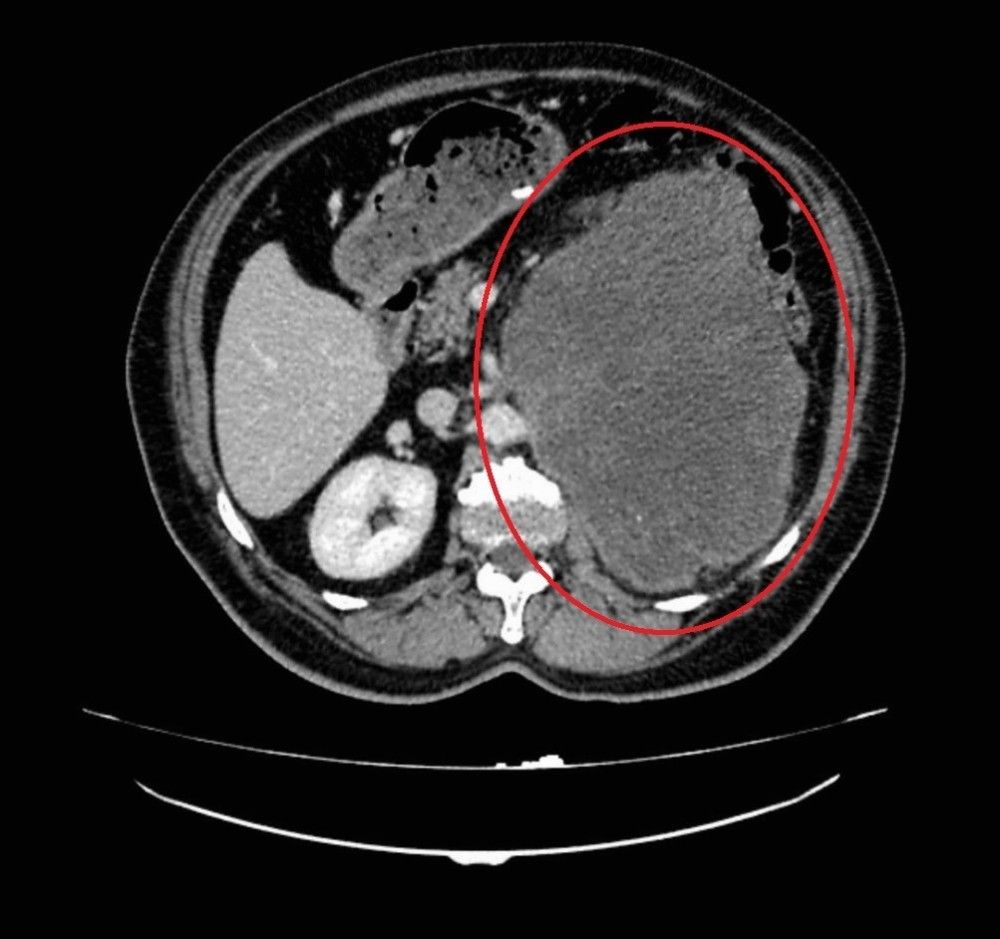

Samsun’da 62 yaşında erkek hasta sol yan ağrısı ve karın şişliği şikayetleri ile OMÜ Tıp Fakültesi Hastanesi Üroloji Kliniğine başvurdu. Hastanın yapılan muayene ve tetkikleri sonucunda böbreğinde 20 santim boyutunda tümör tespit edildi. Başarılı bir ameliyatla çıkarılan kitlenin patoloji sonucu miksofibrosarkom olarak saptandı. Normalde kol ve bacaktaki yumuşak dokulardan kaynaklanan bu tümör türünün böbrekte görülmesine oldukça şaşırdıklarını belirten OMÜ Tıp Fakültesi Üroloji Anabilim Dalı Öğretim Üyesi Doç. Dr. Berkan Reşorlu, olgularını 2015 yılında İspanya’da görülen vakanın ardından dünyada görülen ikinci vaka olarak ürolojinin prestijli dergilerinden birinde yayınlattıklarını belirtti.

Yapılan operasyon ve hasta hakkında bilgi veren Doç. Dr. Berkan Reşorlu, "Hastamız sol yan ağrısı ve karında şişlik şikayeti ile bize başvuran 62 yaşında bir erkekti. Yaptığımız muayene ve radyolojik görüntülemeler sonucunda sol böbrekten kaynaklanan 20 santim boyutunda bir kitle olduğunu tespit ettik. Bunun üzerine hastayı ameliyata alarak, başarılı bir operasyonla böbrekle birlikte kitleyi çıkardık. Çıkardığımız kitlenin patoloji sonucu sıklıkla kol ve bacaktaki yumuşak dokulardan kaynaklanan ’miksofibrosarkom’ dediğimiz kötü huylu bir tümör olarak geldi. Böyle bir tümörün böbrekten kaynaklanmasını beklemiyorduk. Literatürü araştırdığımızda böbrekten kaynaklanan tek ’miksofibrosarkom’ vakasının 2015 yılında İspanya’dan bildirildiğini gördük. Bunun üzerine bizde olgumuzu hızlı bir şekilde ürolojinin prestijli dergilerinden birinde yayınlattık ve dünyada görülen ikinci vaka olarak literatüre kazandırdık. Hastamızın kitlesi oldukça büyük, çevre organlara yapışık ve ana damarları tamamen sarmış durumdaydı. Oldukça riskli ve zor bir ameliyatın ardından bu kitleyi çıkartarak kemoterapi tedavisine başladık ve şu an hastamızı yakın takip altında tutuyoruz. Böbrek tümörleri, ürolojide prostat ve mesane kanserlerinin ardından en sık izlenen 3. kanser türü ve son yıllarda görülme sıklığı tüm dünyada artıyor. Tüm kanserlerde olduğu gibi bunlarda da erken tanı oldukça önemli. Ancak bu kanser türü sıklıkla tesadüfen saptanıyor. Çünkü hastaların ancak yüzde 10-15’lik kısmında idrardan kan gelmesi, karında şişlik ya da yan ağrısı gibi şikayetlere yol açıyor. Kendilerinde bu tip belirtiler izleyen hastaların vakit kaybetmeden bir üroloji uzmanına başvurmasını öneriyoruz" dedi.